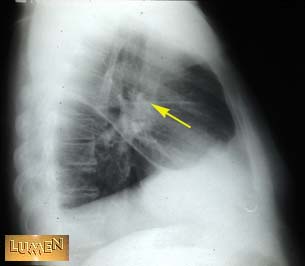

Horizontal fissure.